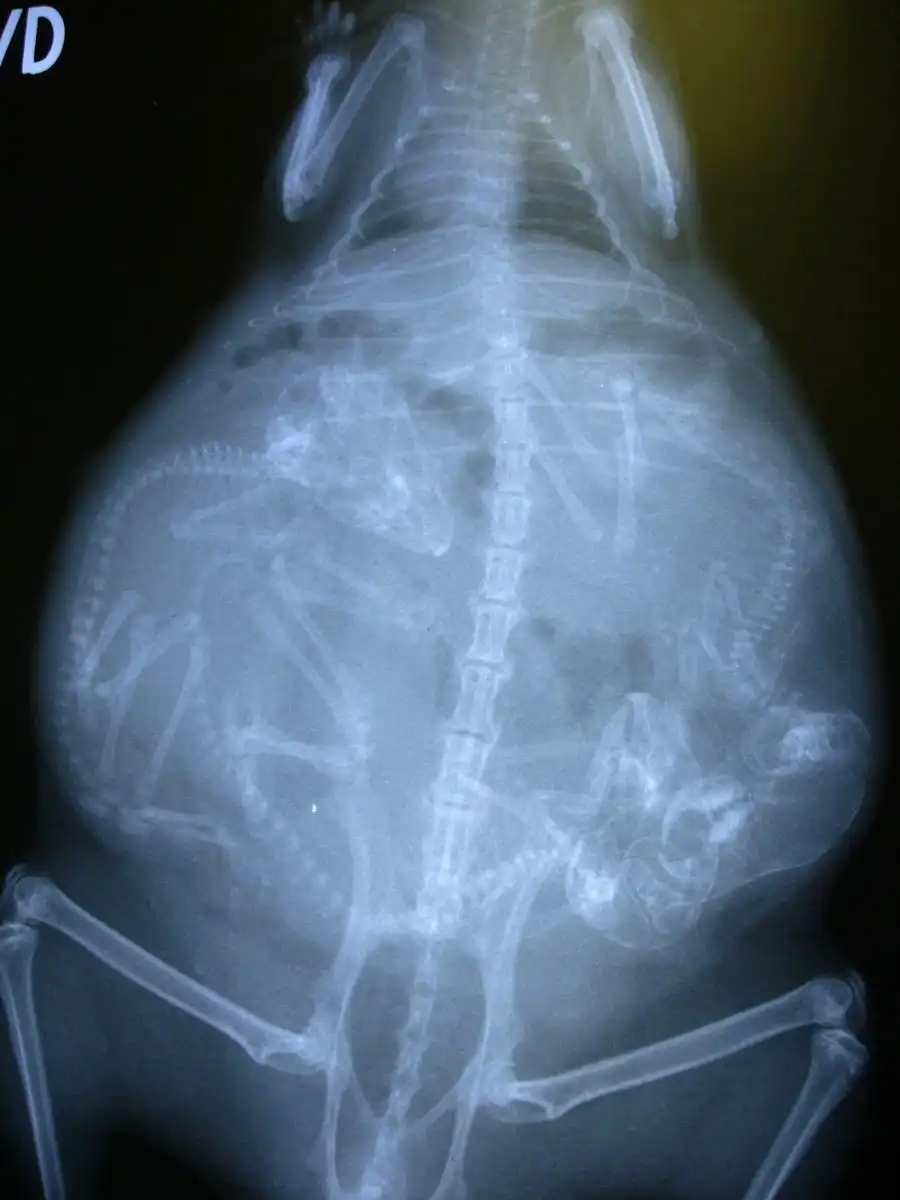

Еще одна беременная морская свинка